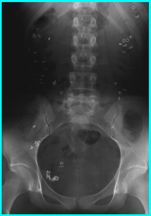

Rallentato Transito Intestinale

Questa forma è caratterizzata da un ridotta motililità del colon e/o da un colon lungo e tortuoso (dolicocolon). In questo caso si ha una ridotta frequenza di evacuazioni con frequente emissione di feci dure o caprine.